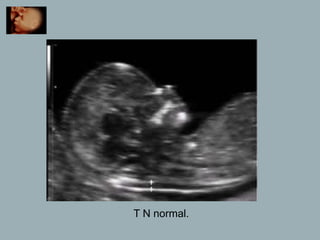

T N normal.